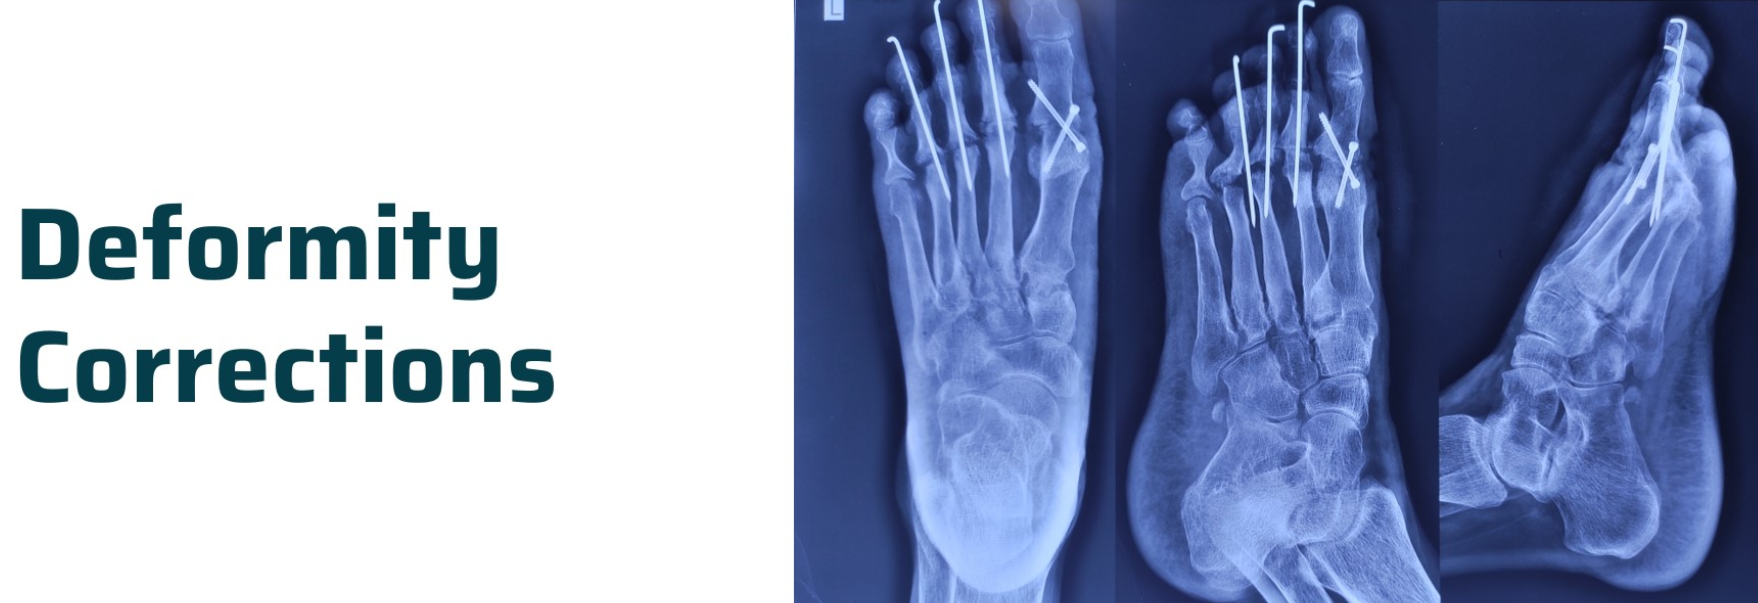

Deformity Correction